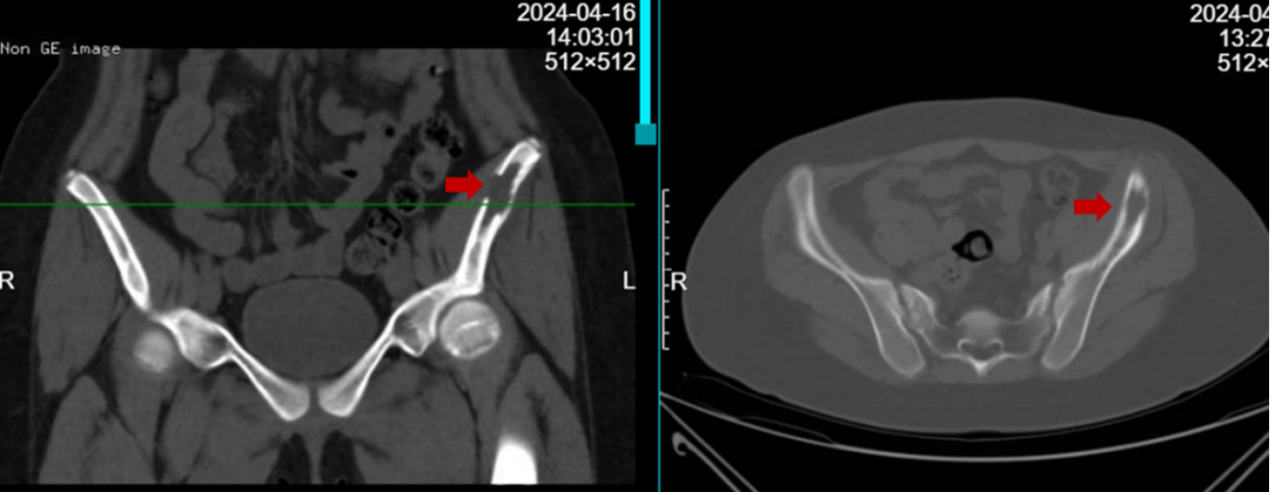

朗格汉斯细胞组织细胞增生症(Langerhans cell histiocytosis,LCH)原名组织细胞增生症,是由于树突状单核细胞增生所致,伴局部或广泛的器官浸润